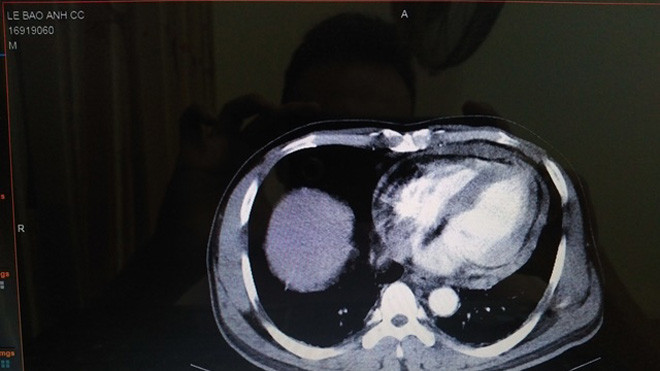

Bệnh nhân bị bằng dao Thái Lan tại khoang liên sườn 5, đường giữa xương đòn trái. Siêu âm và chụp CT cho thấy tràn dịch màng tim, tổn thương rách tụ dịch cơ tim (tâm thất phải vùng mỏm).

Ca phẫu thuật hút ra nửa lít máu ở màng tim và máu vẫn tiếp tục chảy ở vết thương thành thất phải vùng mõm theo nhịp bóp của tim. Các bác sĩ đã dùng màng tim để khâu vết thương tim cầm máu thành công.